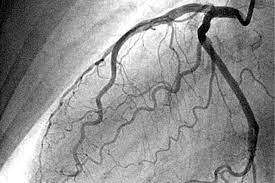

Características clínicas de los síndromes coronarios agudos sin elevación del segmento ST

Los síndromes coronarios agudos constituyen un espectro de isquemia cardíaca inestable que abarca desde la angina inestable hasta el infarto agudo de miocardio. Esta variabilidad en la presentación clínica se…